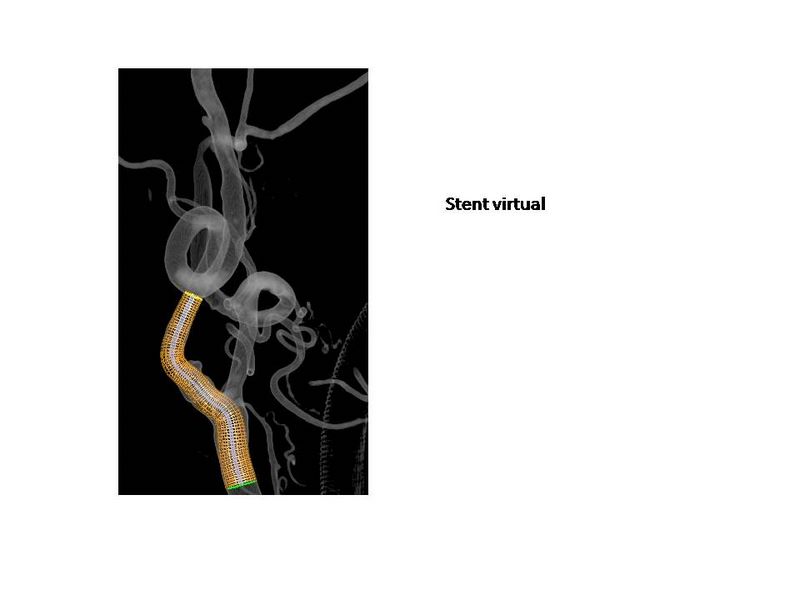

Otro Stent Carotideo